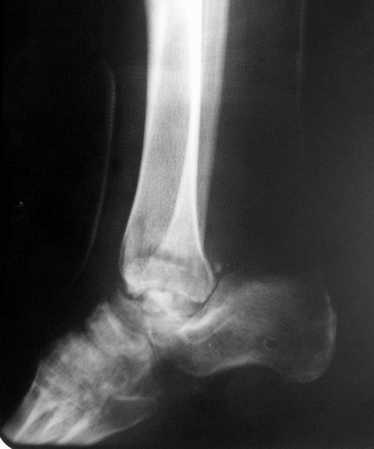

Глубокоуважаемые коллеги! Просим совета в лечении пациента с последствиями тяжелой сочетанной травмы. Пациент С., 41 года, по профессии бизнесмен, в сентябре 2005 г. пострадал в дорожно-транспортном происшествии (упал с мотоцикла). Диагноз: ЗЧМТ, ушиб головного мозга тяжелой степени. Открытый переломо-вывих левой таранной кости. Закрытые переломы лонной и седалищной костей слева. Был доставлен в НИИСП им. Н.В. Склифосовского. При ПХО раны выявлен открытый перелом левой таранной кости (III тип по Hawkins) с утратой вывихнутого тела таранной кости. Выполнена ПХО, фиксация голени и стопы стержневым аппаратом. Рана зажила без осложнений. Аппарат демонтирован через 1,5 месяца. В настоящее время больной предъявляет жалобы на боль в голеностопном суставе при нагрузке. Передвигается с опорой на костыли с дозированной нагрузкой на левую стопу.Голень и стопа фиксированы циркулярной пластиковой повязкой. Сохраняются остаточные явления ЧМТ (в виде сниженной критики к своему состоянию и определенной недисциплинированности в выполнении врачебных рекомендаций) Рентгенограммы – рис. 1, 2 (просим извинения за низкое качество рентгенограмм), схема – рис. 3. В качестве варианта хирургического лечения мы считаем возможным выполнить следующее вмешательство: артродез большеберцовой и пяточной костей в сочетании с артродезом переднего края большеберцовой кости и головки таранной кости с фиксацией спонгиозными винтами. Считаем выполнение артродеза переднего края большеберцовой кости и элементов I луча стопы необходимым для максимального восстановления опороспособности конечности. Однако выполнение операции в указанном объеме привело бы к относительному укорочению внутреннего свода стопы. Мы видим два пути решения данной проблемы: Вариант 1. Применение костного трансплантата (свободного или на сосудистой ножке) для замещения дефекта головки таранной кости и сохранения геометрии внутреннего свода стопы (рис 4). Преимущество: относительная простота операции. Недостаток: высокий риск замедленной консолидации или лизиса трансплантата. Вариант 2. Резекция участка пяточной кости с последующим остеосинтезом винтами для укорочения наружного свода стопы (рис 5, 6). Преимущества: сохранение собственного кровоснабжения всех синтезируемых участков костей. Недостатки: дополнительная травматизация, усугубление деформации стопы в виде нарушения наружного свода. Будем признательны за ваши предложения, включая возможные альтернативные варианты лечения.Заранее благодарны за добрые советы и поддержку. А. Федосов, О. Диденко, П. Иванов. Отделение множественной и сочетанной травмы НИИСП им. Н.В. Склифосовского, г. Москва.

Ваша дискуссия заставила перелистать свои наблюдения.

Среди повреждений таранной кости (Hawkins III-IV) с одновременной травмой лодыжек встретилось следующее (см. вложение). Пациент упал в колодец на глубину 10 метров (Х.2002 г.), госпитализирован с диагнозом: з/перелом шейки правой таранной кости (Hawkins IV) с переломовывихом тела назад и кнутри, закрытый перелом внутренней лодыжки и переднего края большеберцовой кости. Оперирован в первые 12 часов после травмы, выполнена открытая репозиция таранной кости, внутренним и передне-внутренними доступами, остеосинтез переломов шейки и тела губчатыми винтами, для реваскуляризации тела таранной кости первичный компрессионный над- и подтаранный артродез. Синтез внутренней лодыжки губчатым винтом. Удаление винтов через 1 год,2 мес. Получен анкилоз указанных суставов с сохранением длины конечности, полная реваскуляризация таранной кости, о чем говорит сращение ее переломов, отсутствие отеков и

цианоза стопы и голени. Компенсаторная подвижность переднего и среднего отделов стопы около 15-20 градусов за счет поперечного (Шопара) сустава стопы. Считаю оправданной подобную тактику, не смотря на угрожаемый прогноз (100% асептический некроз) по классифицкации Hawkins.